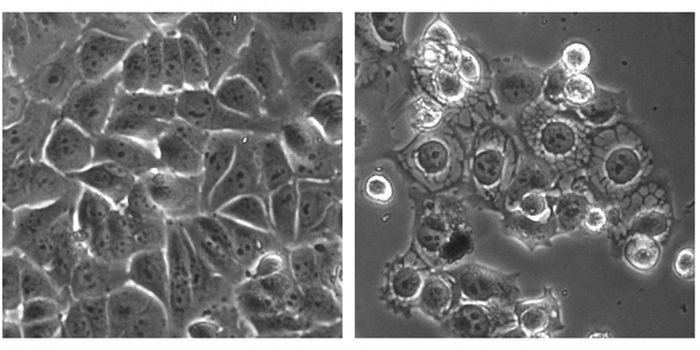

APR 24, 2015Cell & Molecular BiologyResearchers from the Universitat Autònoma de Barcelona (UAB) Department of Cellular Biology, Physiology, and Immunology, ...